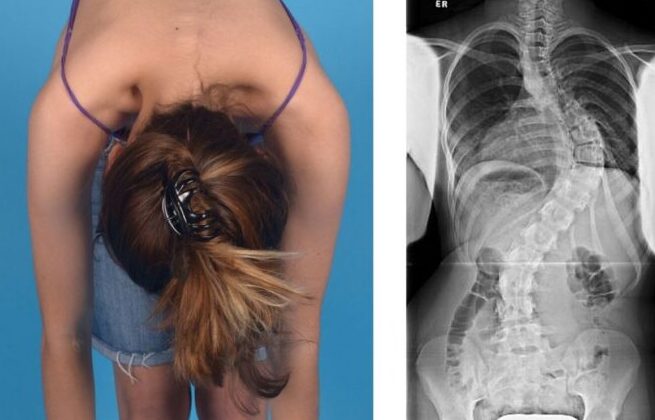

يشعر الكثير من الأهالي والمرضى بالقلق عندما يسمعون أن طفلهم أو أحد أفراد أسرتهم يعاني من اعوجاج العمود الفقري (Scoliosis). من أكثر الأسئلة انتشارًا:

“هل يؤثر هذا الاعوجاج على عمر الشخص؟ وهل يمكن أن يعيش حياة طبيعية؟”

إذا لاحظتِ علامات انحناء في ظهر طفلك، أو لاحظتِ عدم تماثل بين الجانبين، فلا تتردد الأن في استشارة مجانيه من طبيب متخصص.